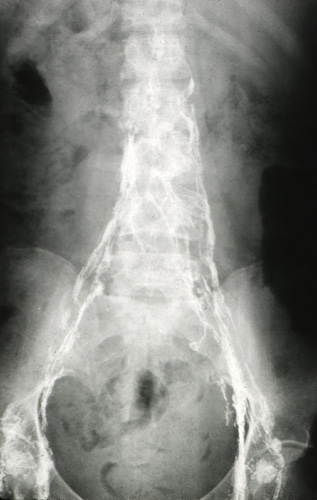

| The lymphatics that drain from the lower extremities past the inguinal regions and into the pelvis are seen here with bright contrast filling the channels in this lymphangiogram. The lymphatics are normally indistinct and carry little lymph fluid, but serve an important function in scavenging fluid and protein not reabsorbe into venules as well as carrying antigens and antigen-presenting cells to lymph nodes to elicit immune responses. |